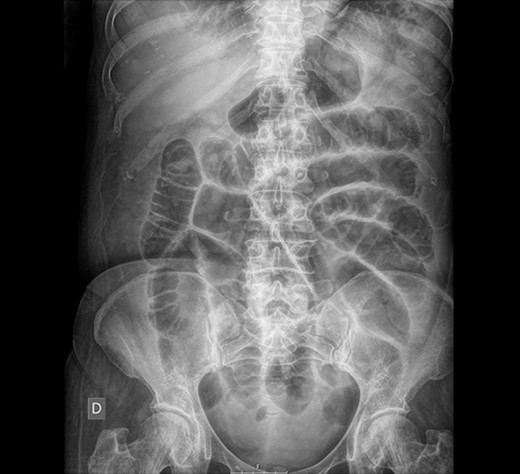

The laboratory results rebelled leukocytosis (15.23x10e3), anemia (9.6 g/dl), neutrophilia (80.4%), band neutrophils in peripheral blood (15%), an elevated C reactive protein (20.62 mg/dl), and procalcitonin (3.92 ng/dl) values (Figs 1 and 2).

Abdominal X-ray: generalized dilatation of the small intestine without distal air in the colon or the rectum.